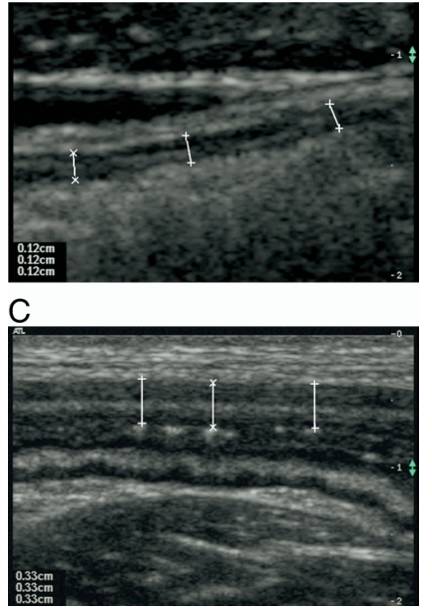

慢性心衰患者肠壁更厚

心衰时肠动脉血流量、肠壁厚度及肠道菌群变化

J Am Coll Cardiol 2014;64:1092–102